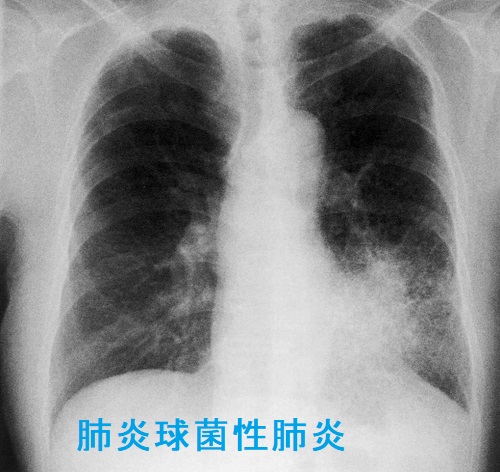

甲状腺と肺炎球菌

甲状腺機能亢進症/バセドウ病で甲状腺ホルモンが正常化していない時に肺炎球菌に感染すると、甲状腺クリーゼをおこし、生命に危険を及ぼす可能性があります。

また、甲状腺ホルモンが正常化していない甲状腺機能低下症/橋本病では肺炎球菌感染により粘液水腫性昏睡に至る可能性もあります。